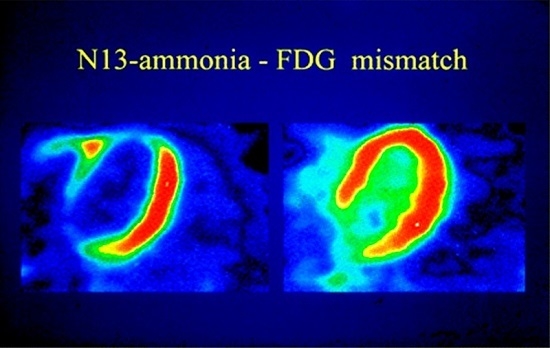

3.2. Myocardial Metabolism and Viability

5.2. Viability and Infarct Assessment